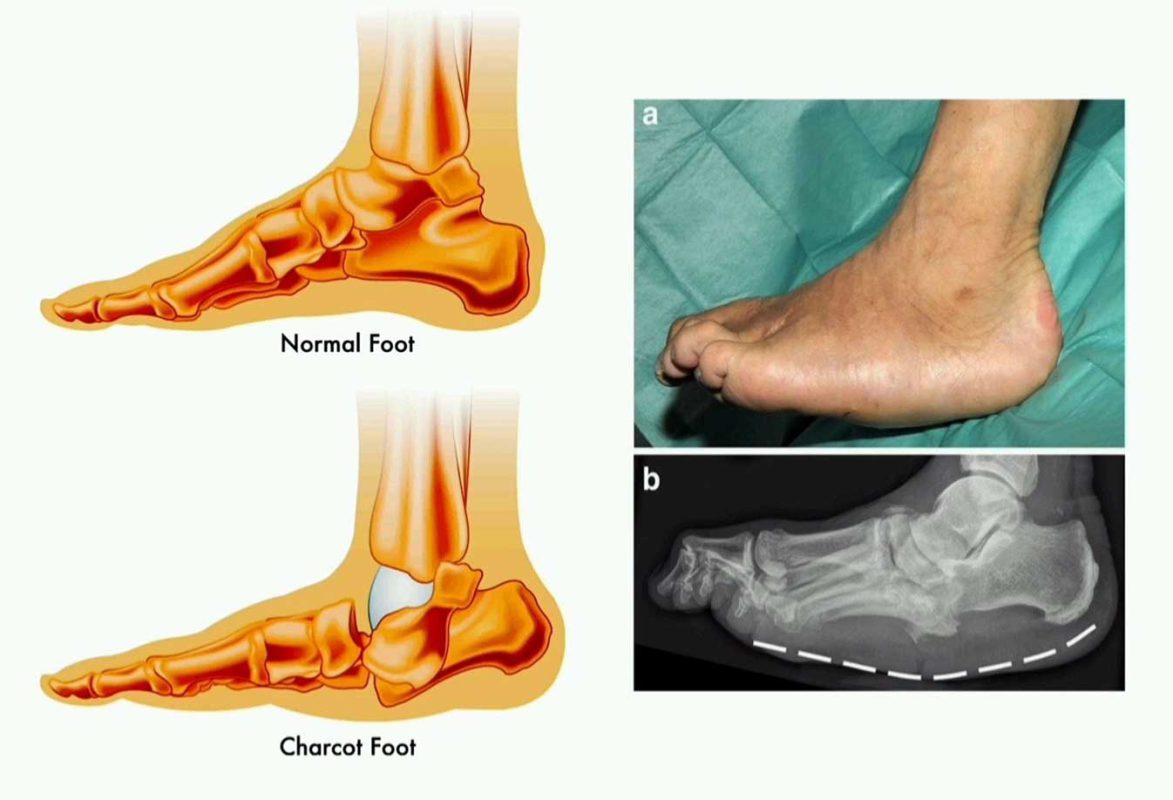

زخم های دیابتی نوعی زخم ها هستند که در افراد مبتلا به دیابت ایجاد می شوند. دیابت می تواند بر جریان خون و عملکرد سیستم ایمنی بدن تأثیر بگذارد و باعث کاهش قابل توجهی در توانایی بدن برای بهبود زخم ها و ترمیم بافت شود. این زخم ها (انواع زخم دیابتی) به طور معمول در پاها، به ویژه در نواحی پاشنه، انگشتان و انتهای اندام ها شکل می گیرند.

زخم پای دیابتی یکی از شایع‌ترین و در عین حال خطرناک‌ترین عوارض بیماری دیابت است که معمولاً در ناحیه کف پا، انگشتان یا پاشنه ایجاد می‌شود. این زخم‌ها به دلیل افزایش مزمن قند خون، آسیب اعصاب محیطی و کاهش جریان خون در پاها به وجود می‌آیند و اگر به‌موقع درمان نشوند، می‌توانند منجر به عفونت شدید، گانگرن و حتی قطع عضو شوند.

در بیماران دیابتی، به علت کاهش حس درد، بسیاری از زخم‌ها در مراحل اولیه تشخیص داده نمی‌شوند و همین موضوع باعث مزمن شدن زخم می‌شود. به همین دلیل، آگاهی از علائم، روش‌های درمان و پیشگیری از زخم پای دیابتی اهمیت بسیار زیادی دارد.